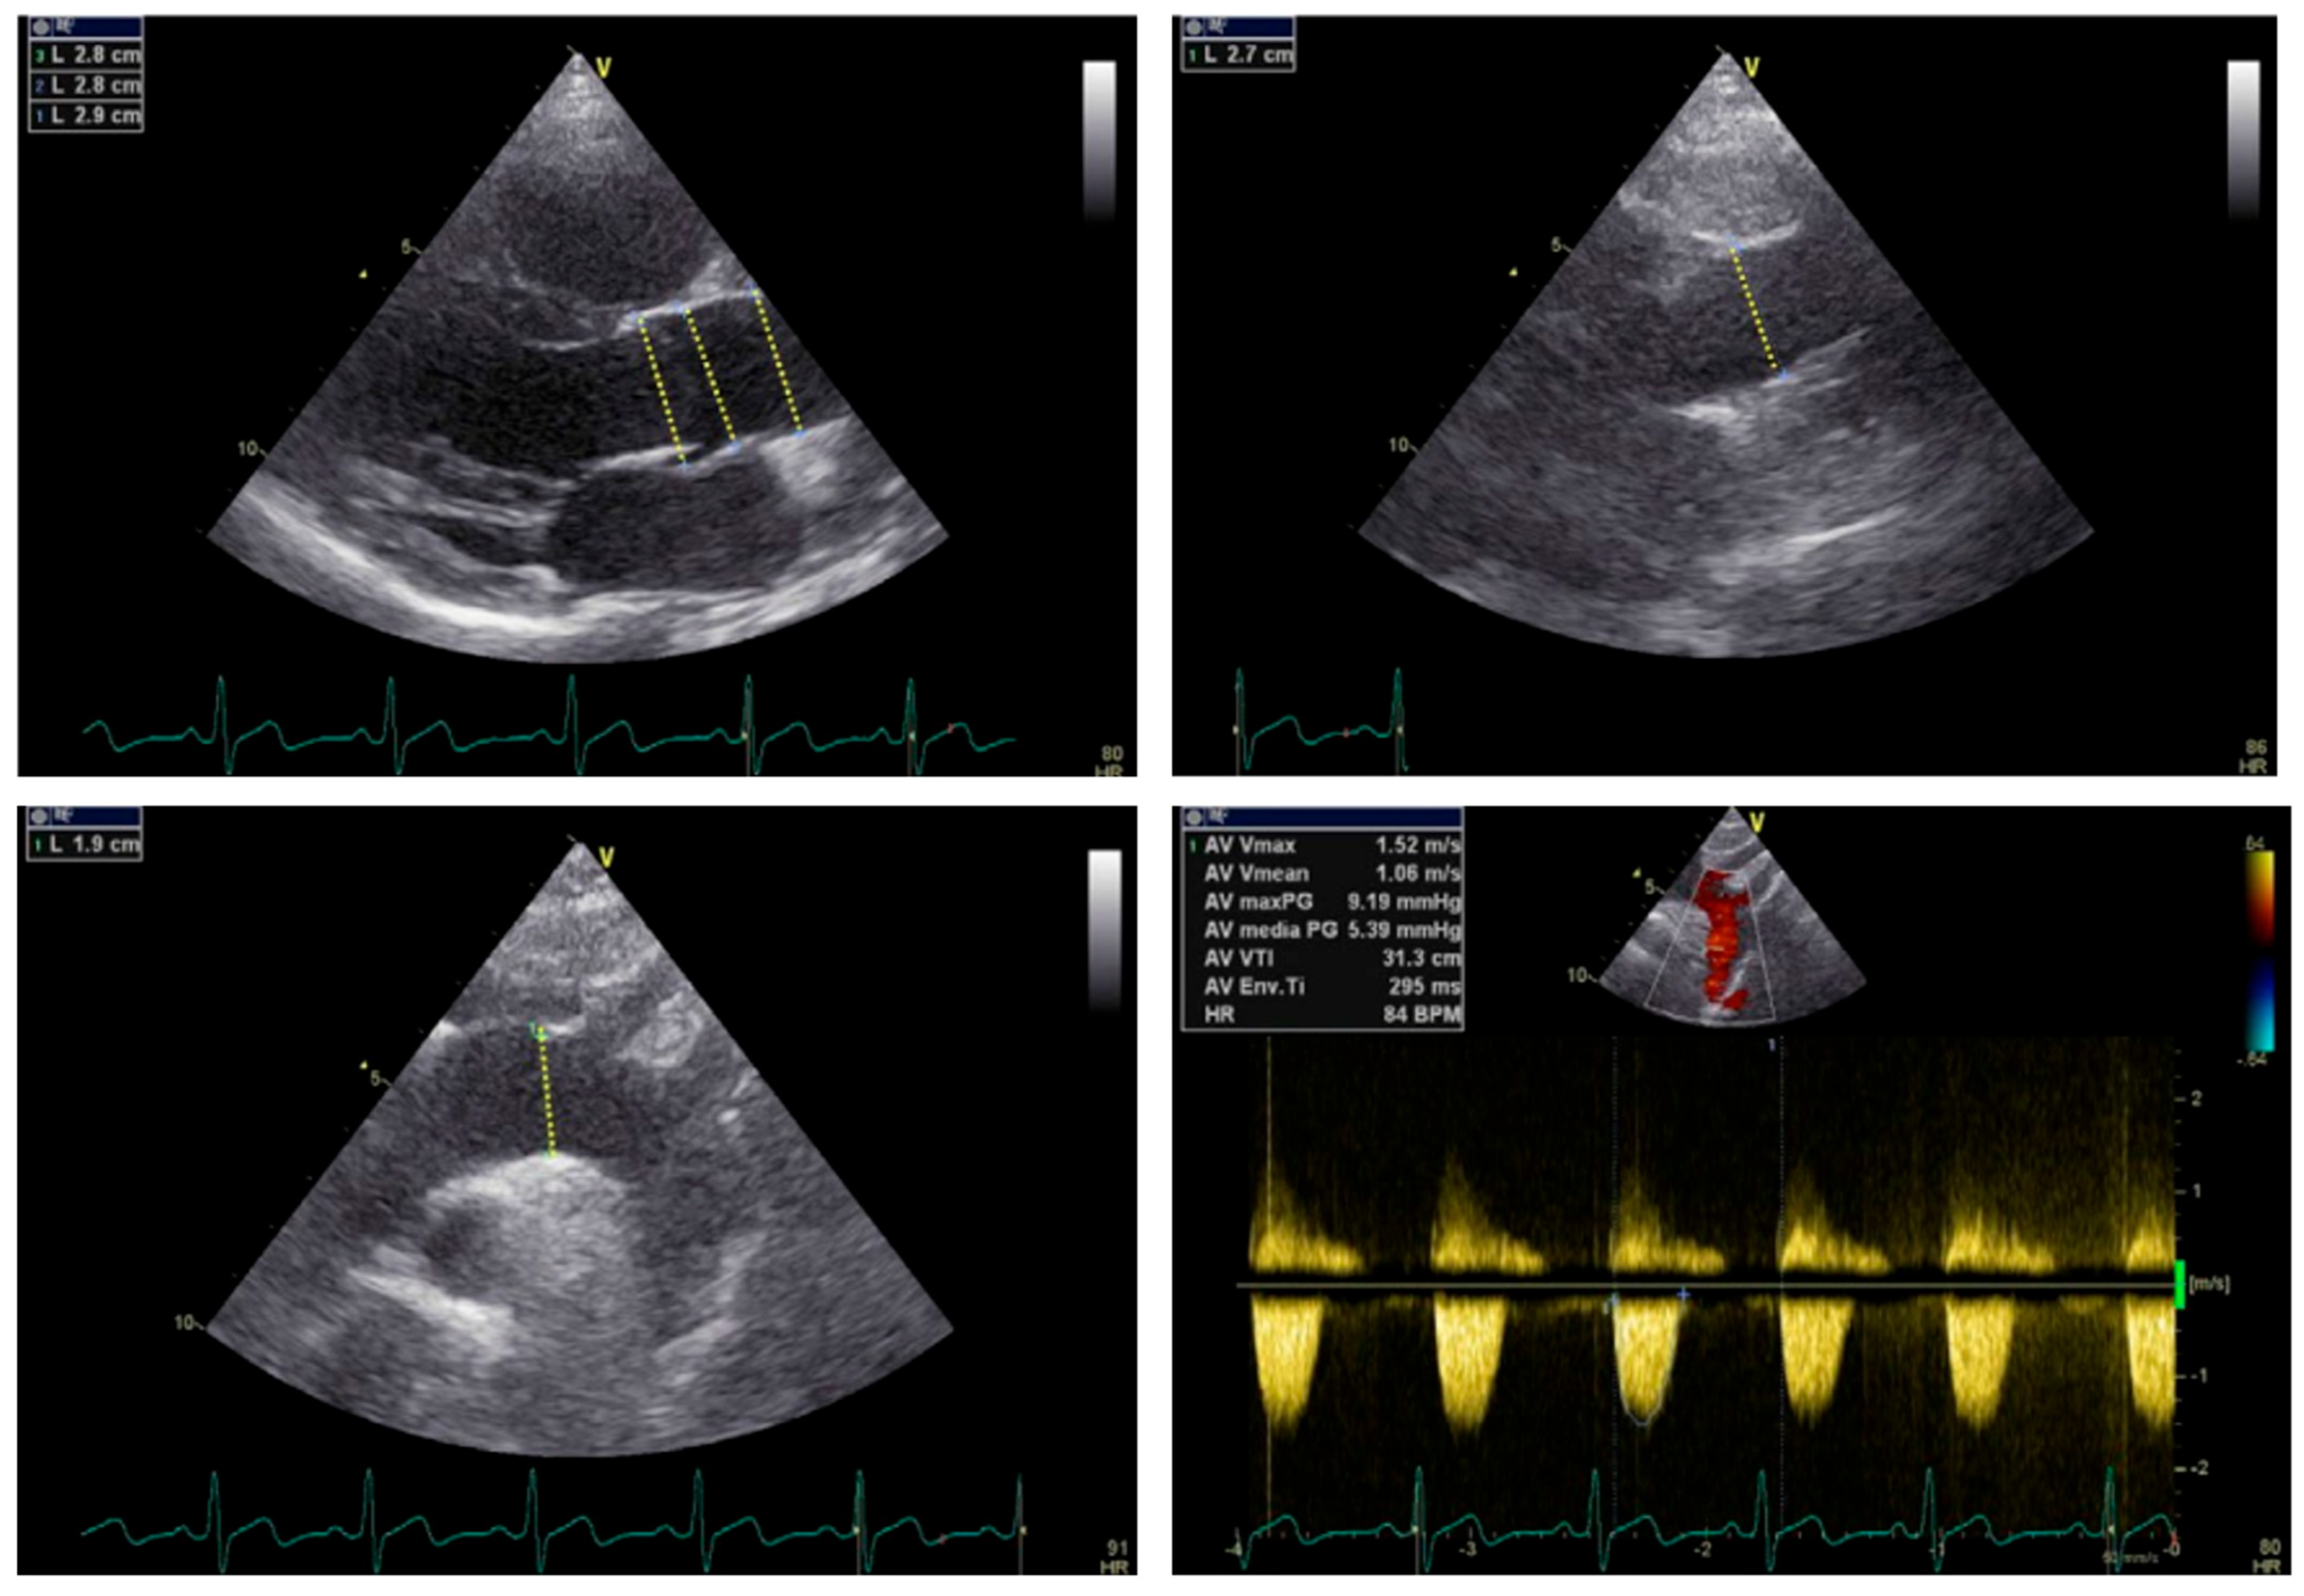

- Plonek, T.; Berezowski, M.; Bochenek, M.; Filip, G.; Rylski, B.; Golesworthy, T.; Jasinski, M. A comparison of aortic root measurements by echocardiography and computed tomography. J. Thorac. Cardiovasc. Surg. 2019, 157, 479–486. [Google Scholar] [CrossRef]